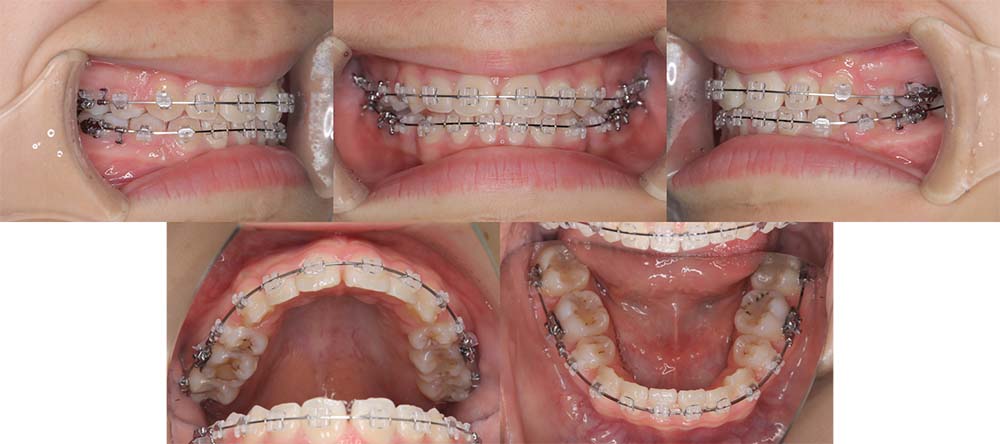

| 症例分類 | 下顎前突、開咬 |

| 診断名 | 上下叢生を伴う開咬 |

| 主訴 | 歯がガタガタ、前歯に隙間があってうまく噛めない |

| 年齢 | 18歳4ヶ月 |

| 性別 | 女性 |

| 抜歯部位 | 右上・左下の第一小臼歯と左上・右下の第二小臼歯 |

| 使用装置 | 表側のワイヤー装置 |

| 治療期間 | 2年9ヶ月 |

| 保定装置 | 固定式保定装置、取り外し式保定装置(8時間) |

| 費用 |

[検査・診断料] ¥49,500 [基本施術料] ¥792,000 [調整料] ¥4,400/回 [抜歯] ¥5,500/本 [保定装置] ¥55,000(税込) 抜歯や虫歯治療は他院にて費用が別途かかります。(抜歯¥4,000〜10,000/本)

他院にて「顎変形症のため手術併用での矯正治療が必要である」との説明を受け、当院を紹介されてご来院されました。骨格的にやや受け口傾向ではありましたが、手術を併用せず改善できる旨をご説明し、矯正単独で治療することにしました

上顎右側第一小臼歯、上顎左側第二小臼歯、下顎右側第二小臼歯、下顎左側第一小臼歯を抜去して治療を行いました。

左下は奥歯を前方に移動させる必要があったため、矯正用アンカースクリューと顎間ゴムを使用して噛み合わせを改善しました。左下の前方移動に時間がかかってしまい、治療期間が予定より伸びてしまいましたが、問題なく咬合させることができました。

下顎の親知らずは将来的に抜去した方が良いことを説明しております。